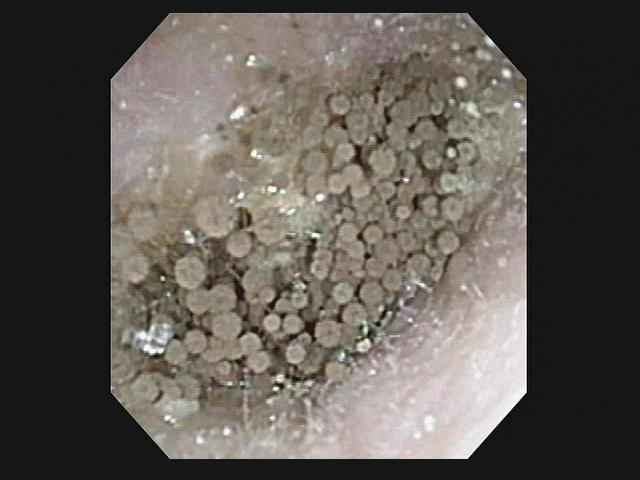

外耳道にカビが生えるメカニズムを説明しよう。まず耳そうじを頻回にしてしまうことだ。皮膚の健康を損なうと、外耳道に傷ができる。次にそこに胞子が付いた耳かきを入れ、胞子が傷につくと傷から水分を得て芽を出す。瘴気こそ出さないがこの芽から菌糸を伸ばしてその先に新しい胞子を作る。

(腐海の様な外耳道の真菌)

顕微鏡でこの外耳道真菌症に出会うと私はとっさに息を止める。そしてナウシカのように「少し、肺に入った」と独り言ちてみる。現実にはカビは普通に空気中を漂っていて毎日肺に入ってるけどね。そして気を取り直して、患者さんに外耳道にカビが生えていることを伝える。この時も「汚れているのは外耳道なんです。カビは悪くない」と心でつぶやきながら。